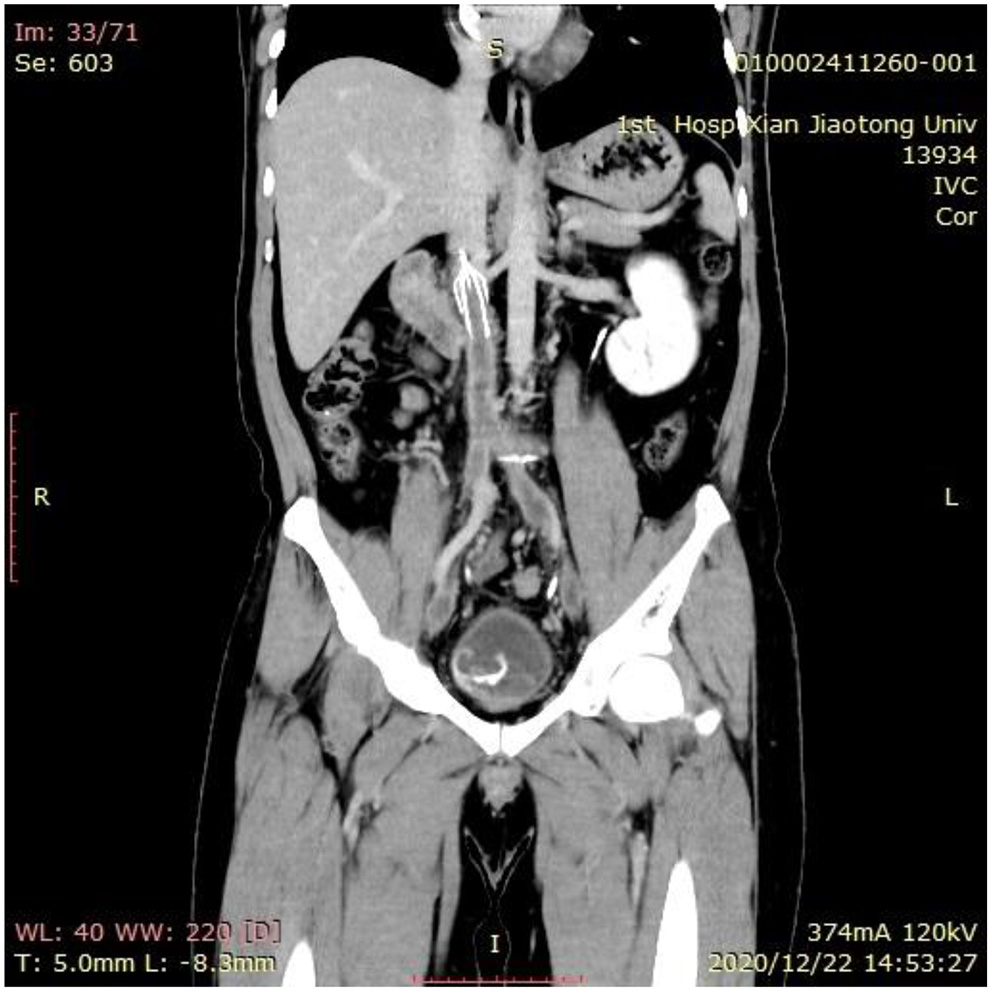

Figure 3

The CT examination of the lower extremity veins showed implantation of the inferior vena cava filter, inferior vena cava and bilateral external iliac vein thrombosis, and bilateral internal iliac vein thrombosis.